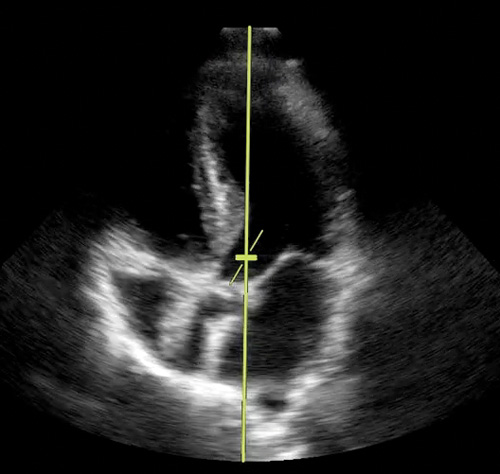

- Đặt đầu dò tại vị trí tiếp theo để có mặt cắt 5 buồng tại mỏm

- Đặt cổng (gate) Doppler tại đường ra thất trái LVOT.

- Ấn nút Doppler DW

- Vẻ đường vòng quanh sóng âm

- Ghi nhận VTI